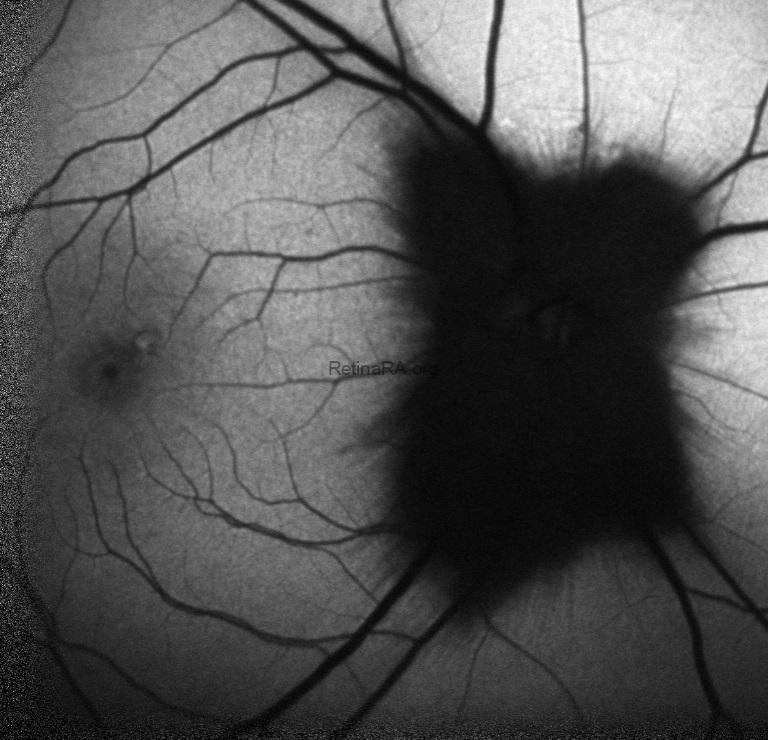

Fundus autofluorescence showed corresponding hypoautofluorescence at the lesion sites.

Myelinated retinal nerve fibers are a rare, benign finding in the eye. Normally, retinal nerve fibers are unmyelinated, but in MRNF, myelin extends into the retina, appearing as white or gray striated patches near the optic disc. They are usually discovered incidentally during routine eye exams and are typically asymptomatic. While vision is often normal, MRNF can sometimes be associated with high myopia or amblyopia. Optical coherence tomography (OCT) shows a thickened, hyperreflective retinal nerve fiber layer corresponding to the lesion. No treatment is needed, but regular monitoring is recommended to rule out other retinal pathologies.